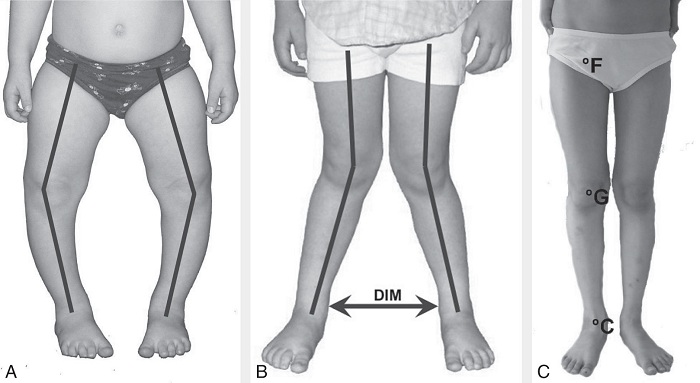

Рекурвация коленного сустава: рентгеновские снимки и объяснения